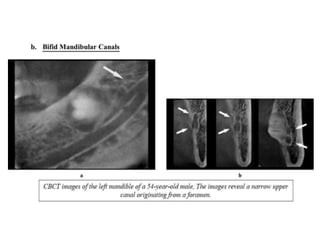

1. Disturbance to the mandibular canal :